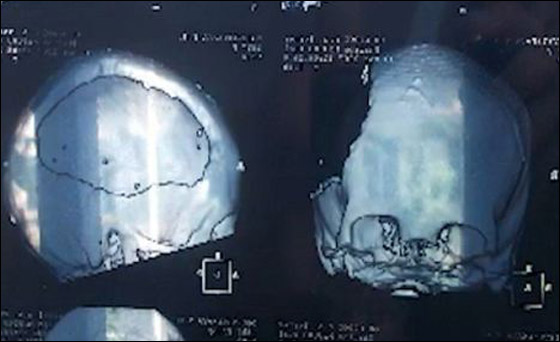

وأجرى الأطباء لها عملية جراحة لإزالة الجزء الأيسر من المخ المسؤول عن المنطق والتحليل، ووضع طبقة واقية داخل المخ، لكنهم لم يضعوا أملاً كبيرًا في شفائها، وأبلغوا والدتها أنها ربما تبقى مصابة بإعاقة حركية طول عمرها. ورغم ذلك لم تستسلم الأسرة لتوقعات الأطباء، وبدأت في تقديم الدعم النفسي للفتاة التي نجحت تدريجيًّا في استعادة قدرتها على الكلام.